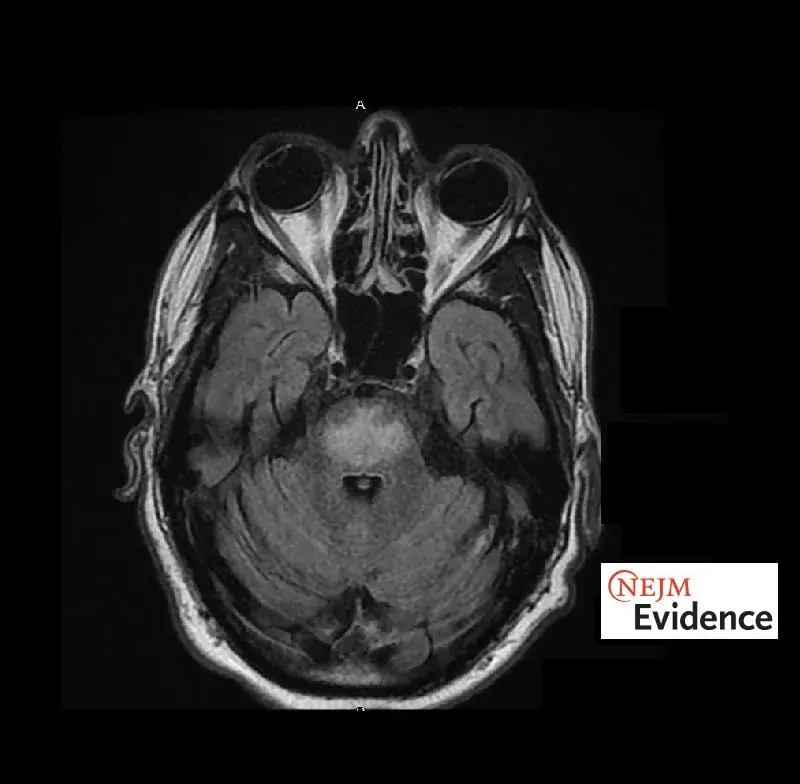

Síndrome da Desmielinização Osmótica: Rara, mas potencialmente grave!

Síndrome da Desmielinização Osmótica: Rara, mas potencialmente grave!